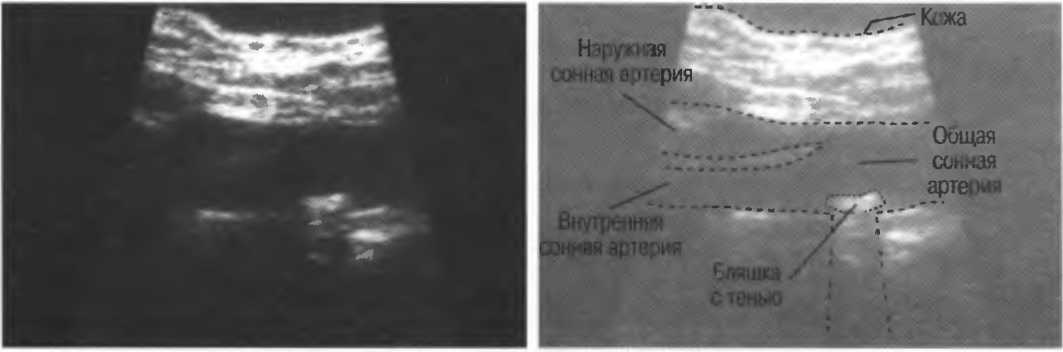

Рис.2в. Дуплексное доплеровское сканирование внутренней сонной артерии. В левой половине представлена кривая скоростей кровотока, демонстрирующая пульсирующий поток по направлению к датчику. Если бы поток был направлен от датчика, то спектр скоростей кровотока был бы направлен вниз от изолинии. Кривая скоростей носит волновой характер в соответствии с сердечным циклом. В правой половине развертки представлено изображение в В-режиме, которое показывает, откуда был снят спектр скоростей кровотока.

Рис.2г. Результаты исследования могут быть искажены, если угол сканирования выбран неправильно. Это та же общая сонная артерия, представленная на рис. 2в, однако угол сканирования составляет около 90°. В результате поток выглядит турбулентным, хотя на самом деле он совершенно нормален. В данном случае неправильно выбран угол сканирования, а с потоком все в порядке.